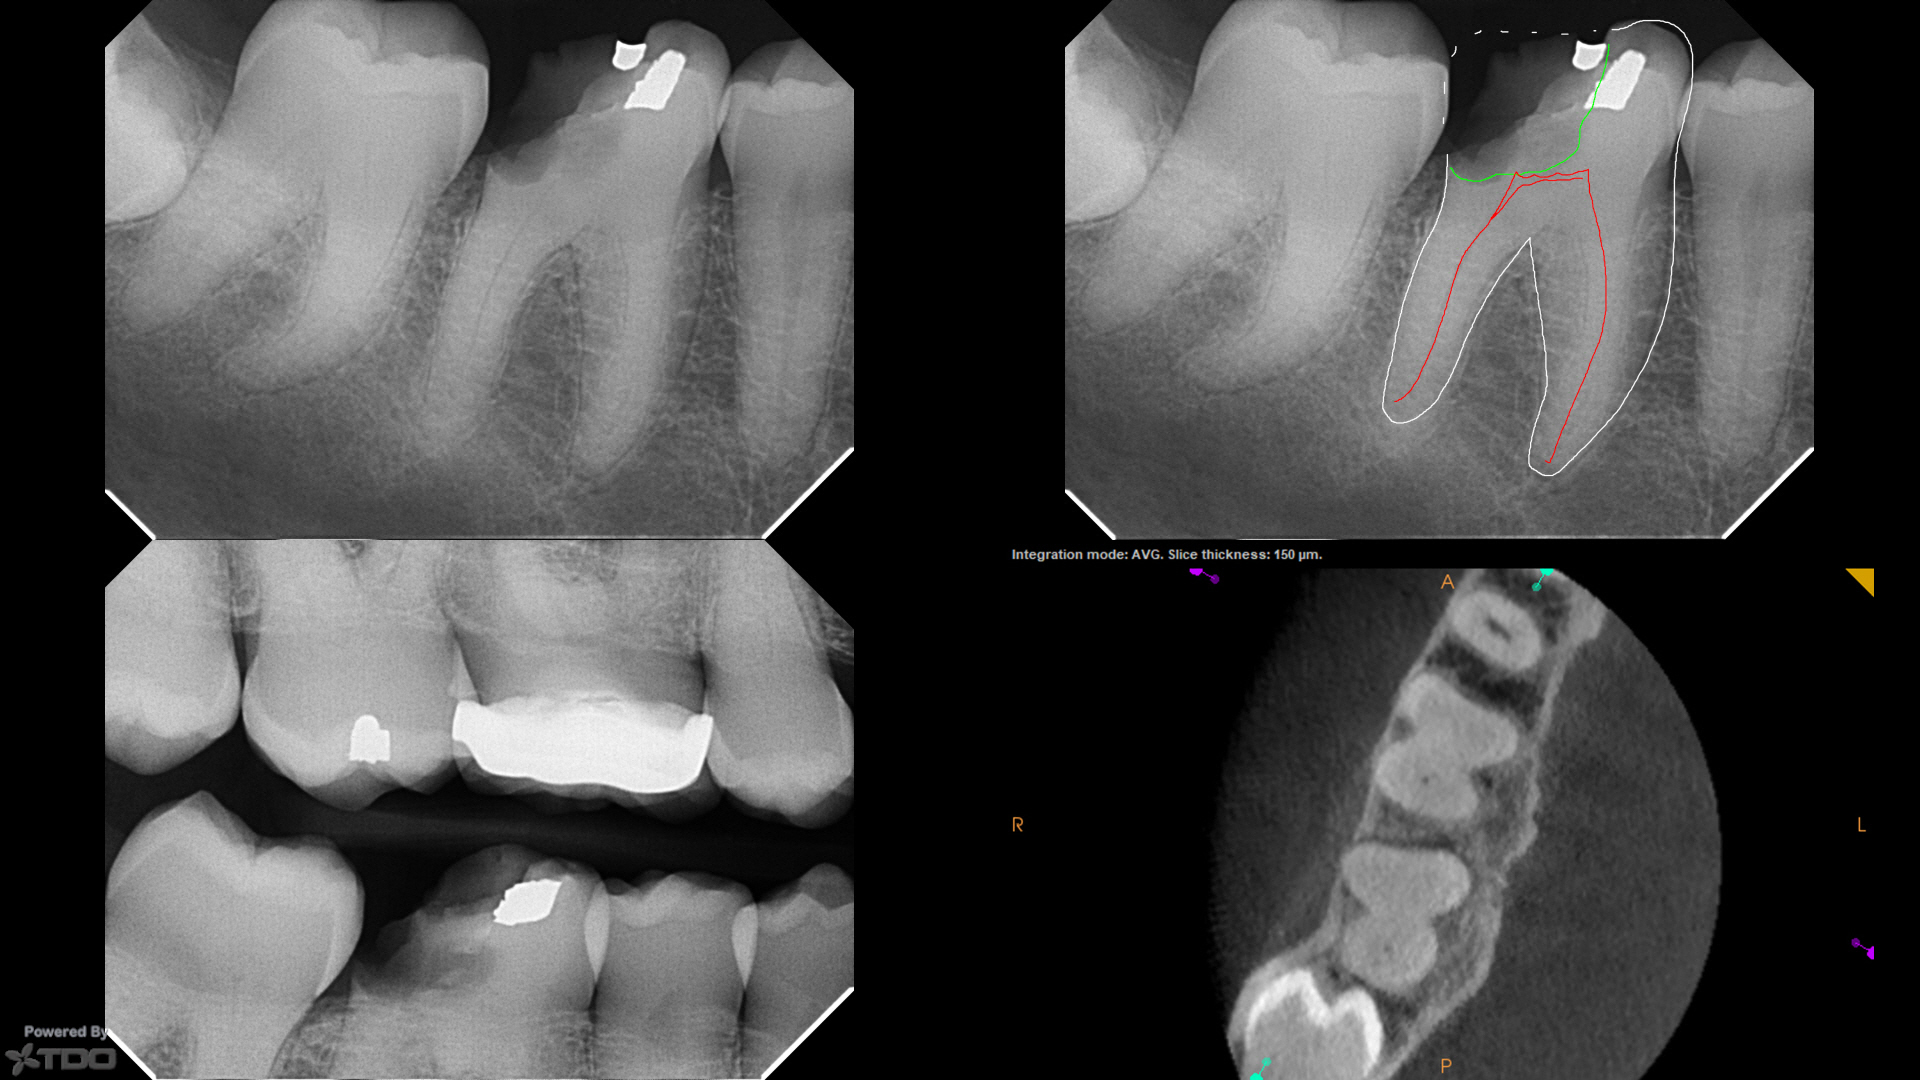

Completely calcified tooth does not necessarily condemn it to extraction November 4 2015 By Dr Pierre Pizem 6 Comments One must not decide a tooth extraction on the sole basis of an x. Even if your calcified tooth cannot be treated with a traditional root canal your endodontist may still be able to save your tooth with a calcified root canal.

In cases of complete root canal system obliteration by calcifications it is extremely difficult to locate.

Adherent calcifications do represent a significant challenge in endodontic procedures. In cases of complete root canal system obliteration by calcifications it is extremely difficult to locate. Can a Calcified Tooth Be Saved.

If there is a decalcified area around the apex andor there is pain do the endo. Our in-house 3-D imaging operating microscopes and experience help us immensely with these challenging teeth. For more information on how endodontic retreatment can treat a calcified tooth root and save your tooth contact Seattle Endodontic Arts.